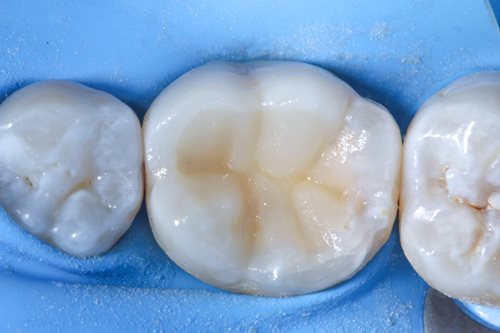

Initially, the patient was treated in a general dental practice where the doctors detected deep secondary caries closely located to the dental nerve of a bottom left molar. Since preserving the vitality of the tooth nerve was top priority, the patient was directly referred to Georg Benjamin’s specialized endodontic practice to undergo treatment.

Dr. Benjamin diagnosed a symptomatic reversible pulpitis and initially performed a cold test to determine whether the dental nerve was still fully vital. As the cold test turned out positive, Dr. Benjamin decided to perform a partial pulpotomy to remove the deep secondary caries and preserve the vitality of the tooth nerve.

Since the infected bottom left molar already contained a filling, Dr. Benjamin removed the old filling material with the help of a diamond bur. After this, he removed the secondary caries by using an EndoTracer, but then switched to a hand instrument to precisely clean the remaining tooth substance.

After complete removal of the secondary caries, a partial pulpotomy of the infected but still viable dental nerve was carried out by creating an access cavity with a bur in order to gain access to the mesial pulp horn. To open the mesial pulp horn, Dr. Benjamin used a new sterile instrument to minimize the risks of infection. This was followed by a millimeter accurate excision of the pulp horn, making sure that the pulp horn is removed evenly to create a levelled surface area for the Komet BioRepair putty filling material that is applied later.

After selective etching and the composite shaping took place with hand instruments and a small brush. He used tooth colours to create realistic depth of colour and let the filling look like a natural, healthy tooth surface. As a last step, he polished the whole treatment area and performed a bite test. The positive result marked the end of a completely successful treatment.

Having completed the endodontic treatment successfully, Dr. Benjamin was able to preserve his patient’s tooth and prevent tooth loss. Thanks to the BioRepair putty material, the vitality of his patient’s tooth could be preserved, and the application of tooth colours ensured an aesthetically pleasing result.